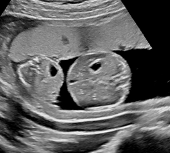

La restrizione selettiva della crescita nei gemelli (sFGR) interessa circa il 10-15% delle gravidanze monocoriali.

La restrizione selettiva della crescita nei gemelli (sFGR) interessa circa il 10-15% delle gravidanze monocoriali (MC). La diagnosi si basa sull’osservazione che uno dei gemelli, quello più piccolo, presenta un peso stimato al di sotto del 10° percentile, senza evidenza di TTTS.

La causa principale di questa condizione è una distribuzione ineguale della placenta tra i due feti. Di conseguenza, il gemello affetto da sFGR dispone di una porzione placentare molto ridotta, generalmente inferiore al 20% del totale. Tuttavia, grazie alle anastomosi vascolari con il co-gemello, il feto con sFGR riesce a mantenersi in vita nell’utero.